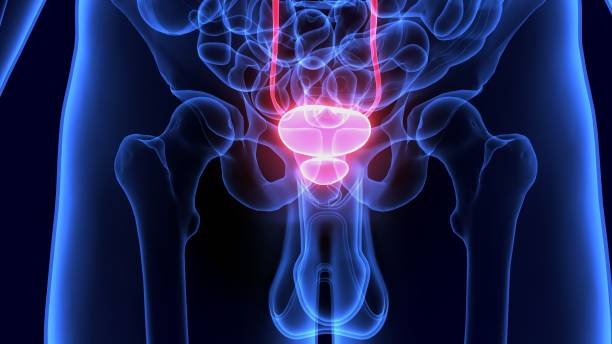

전립선비대증은 남성에서 주로 발생하는 전립선의 비대증입니다. 전립선은 남성의 생식기로서, 요도 주변에 위치하며, 요도를 통해 배뇨와 정액의 배출을 조절합니다. 전립선비대증은 나이가 들수록 발생 확률이 높아지며, 대부분의 남성이 한 번 이상 경험하게 되는 질환입니다.

전립선비대증은 전립선의 세포가 비정상적으로 증식하면서 발생합니다. 이러한 세포 증식으로 인해 전립선이 커지면서 요도 주변을 압박하고, 배뇨와 관련된 증상을 유발합니다. 전립선비대증은 일반적으로 배뇨 불편, 방광염, 자주 병원가는 등의 증상을 유발합니다.